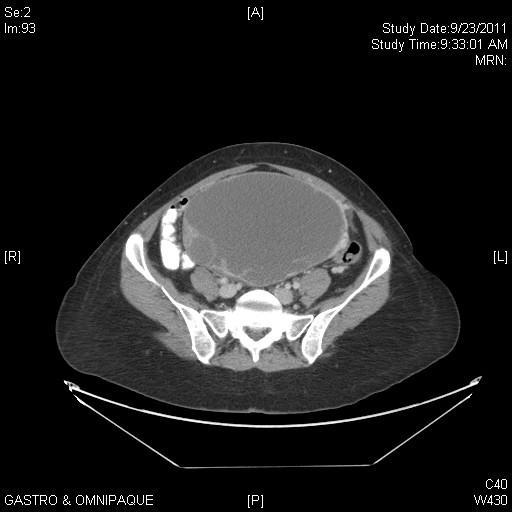

“Suspicious” masses

54yo (CA125=21)

Serous cystadenoma

48yo (CA125=104)

Endometriosis

47yo (CA125=47) Serous adenoca

32yo (CA125=20) Mucinous BT

21yo (CA125=21)

Serous BT